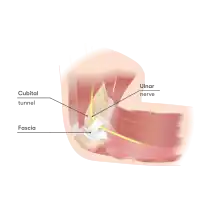

| Cubital tunnel | |

The cubital tunnel is a space of the dorsal medial elbow which allows passage of the ulnar nerve around the elbow. It is bordered medially by the medial epicondyle of the humerus, laterally by the olecranon process of the ulna and the tendinous arch joining the humeral and ulnar heads of the flexor carpi ulnaris.[1] The roof of the cubital tunnel is elastic and formed by a myofascial trilaminar retinaculum (also known as the epicondyloolecranon ligament or Osborne band).[2] In 14% of individuals, the roof of this tunnel is covered by epitrochleoanconeus muscle, a variant muscle.[3]